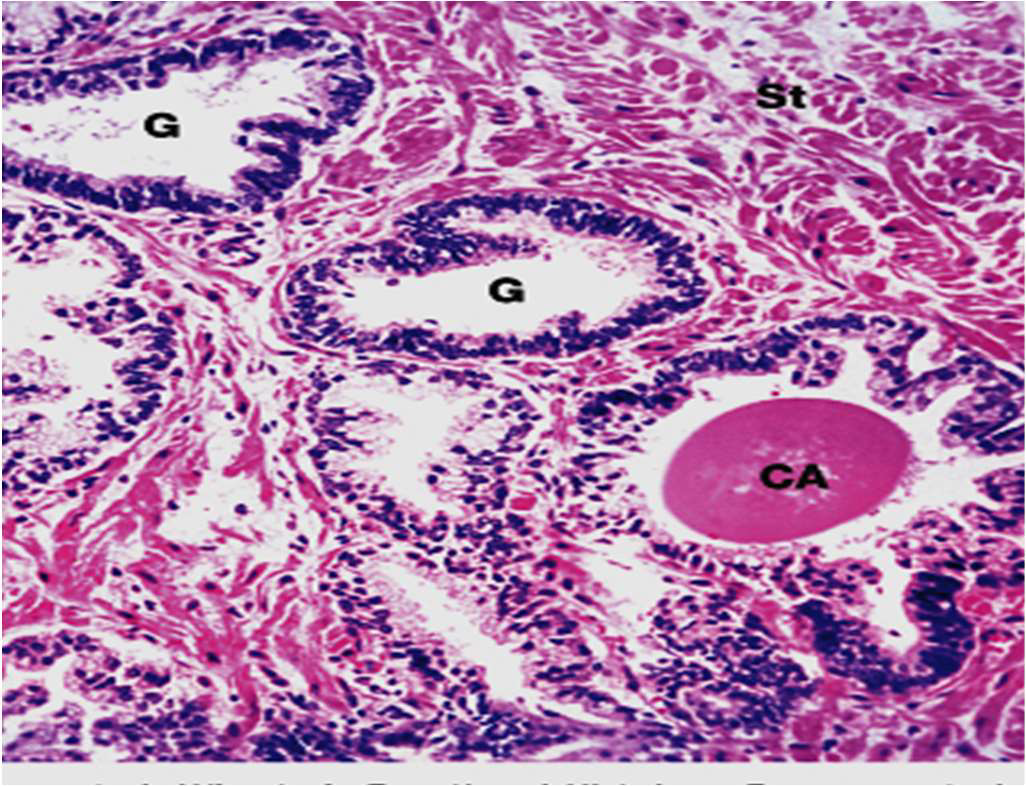

Prostate Gland

- Peripheral zone

- Transitional zone

- Prostatic concretions (CA)

- 年輪狀,填在線體裡面